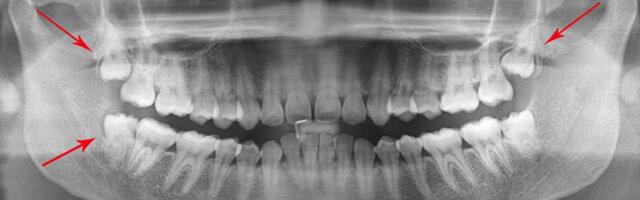

Tarkusehammastest – kas nende eemaldamine on vajalik ja mõttekas?

Tavaliselt meie keha ei kasvata suvalisi ebavajalikke osi – igal kehaosal ja organil on täita oma funktsioon. Kuna kõik meie kehas on omavahel seotud, siis mõjutavad erinevad kehaosad ja organid üksteist mitmel eri viisil ning selle tasakaalu muutmine võib kaasa tuua ettenägematuid tagajärgi. See kehtib ka hammaste kohta. Osas riikides on levinud soovitus eemaldada tarkusehambad ka ...